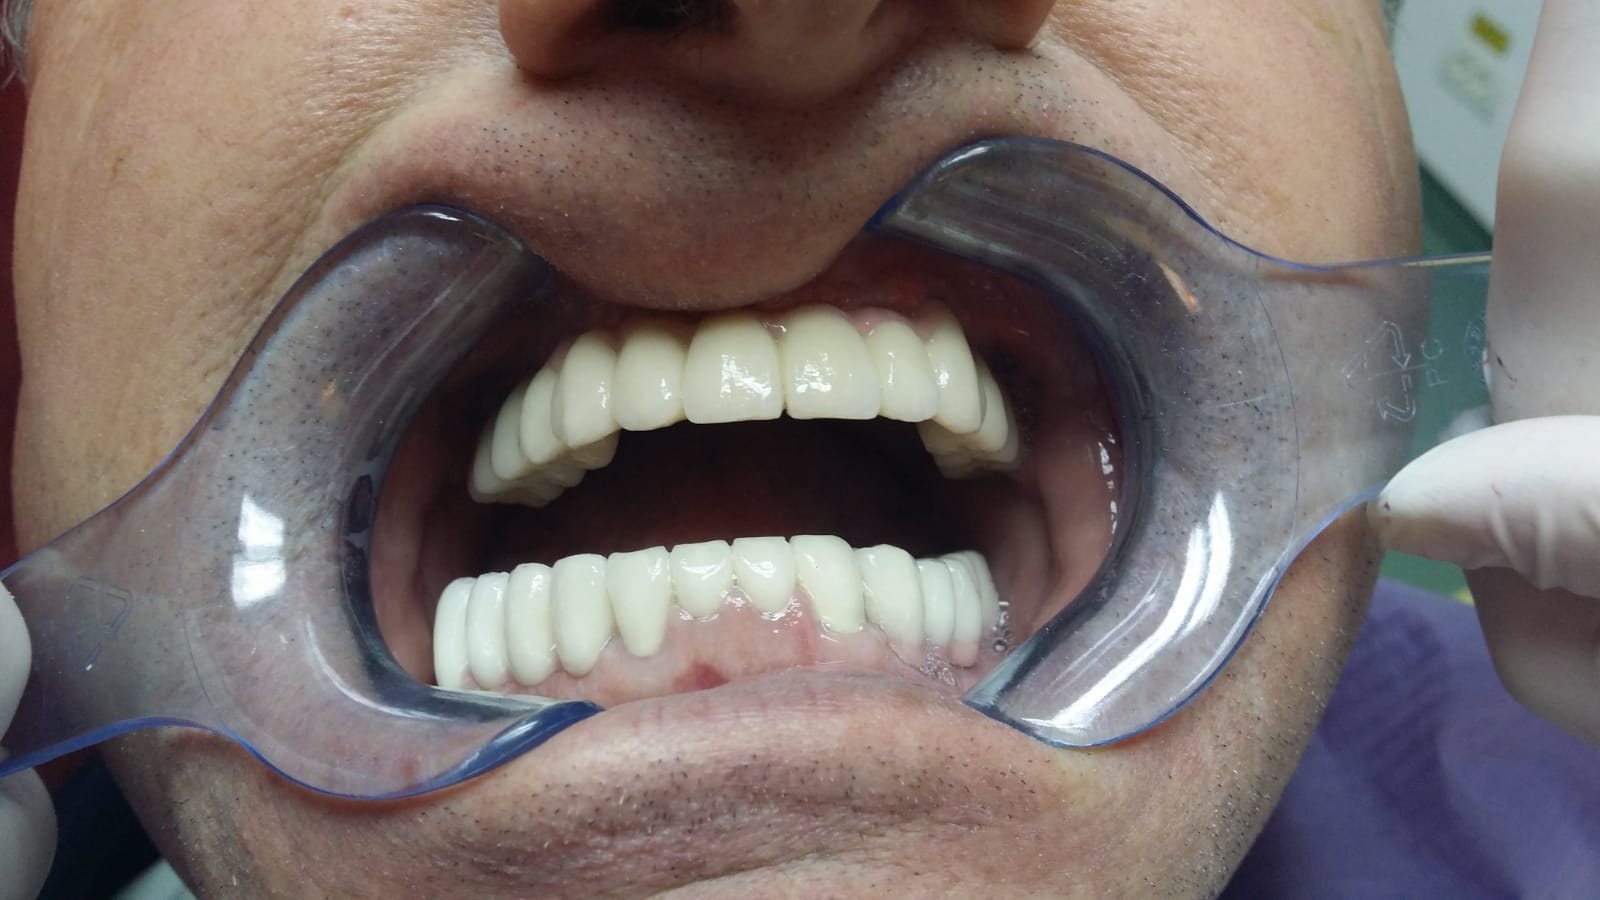

Implant dentar Fast & Fixed ( dantura fixa intr-o zi )

Sistemul de implaturi fast&fix ajuta pacientul sa-si recapete zambetul in mai putin de 24 ore

Pacientului i se insereaza implanturile dentare pe care se fixeaza lucrarea dentara (presupune extractie,implantare si realizarea lucrarii fixe imediat)

La finalul sedintei ,pacientul paraseste clinica cu implanturi si dinti ficsi, fiind capabil sa se reintoarca imediat la viata sociala

Punte realizată pe 4 implanturi dentare la mandibula și 6 implanturi la maxilar All in One